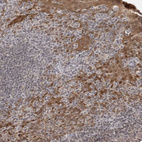

Immunohistochemical staining of human cerebral cortex shows moderate cytoplasmic positivity in neurons.